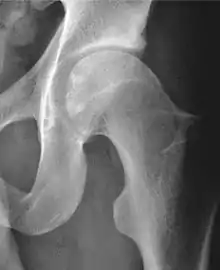

Femoroacetabular impingement (FAI) is a condition involving one or more anatomical abnormalities of the hip joint, which is a ball and socket joint.[1] It is a common cause of hip pain and discomfort in young and middle-aged adults.[2] It occurs when the ball shaped femoral head contacts the acetabulum abnormally or does not permit a normal range of motion in the acetabular socket.[3] Damage can occur to the articular cartilage, or labral cartilage (soft tissue, ring-shaped bumper of the socket), or both.[4] The condition may be symptomatic or asymptomatic. It may cause osteoarthritis of the hip.[1] Treatment options range from conservative management to surgery.[5]

Three types of FAI are recognized (see title image). The first involves an excess of bone along the upper surface of the femoral head, known as a cam deformity (abbreviation for camshaft, which the shape of the femoral head and neck resembles). The second is due to an excess of growth of the upper lip of the acetabular cup and is known as a 'pincer' deformity. The third is a combination of the two, generally referred to as 'mixed.' The most common type seen, approximately 70% of the time, is the mixed type.[13] A complicating issue is that some of the radiographic findings of FAI have also been described in asymptomatic subjects.[14]